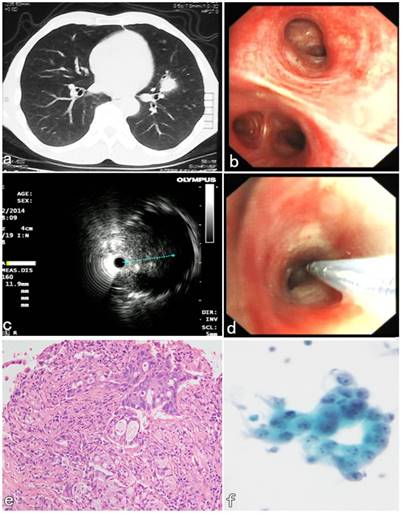

A 55-year-old male patient presented with symptoms of hemoptysis for 10 days. CT confirmed a peribronchial lesion with 11 × 8 × 9 mm in size and located in the lingular lobe of Left upper lobe (Figure 3a). Initial bronchoscopic airway exam was normal (Figure 3b), and the lumen of segmental bronchi was patent. The endobronchial lavaging and brushing were performed and both cytological results were negative. Then the second diagnostic bronchoscopic procedures with R-EBUS assisted C-TBNA was performed 2 days later. R-EBUS was used to reach a peribronchial lesion in the orifice B5 segment of LUL. The ultrasonic imaging from radial probe showed a peribronchial solid nodule with continuous clear edge, and 11 mm in the maximum diameter (Figure 3c). After the needle puncture site with angle was confirmed by R-EBUS, the radial probe was pulled out, then the TBNA needle with 19G in size was inserted through the working channel of the bronchoscope. The “jabbing technique” of C-TBNA needle puncture was performed according to the initial evaluation of R-EBUS (Figure 3d). Satisfactory specimens were obtained, and the histopathological results of C-TBNA showed adenocarcinoma (Figure 3e). The non-small cell cancer cells were found in the cytological results of C-TBNA (Figure 3f). The patient underwent thoracic surgery 5 days later. It was confirmed that pathology of the surgical specimen was consistent with the result of C-TBNA. The final diagnosis of low-differentiated primary adenocarcinoma of LUL was confirmed by immunohistochemical result subsequently.

Figure 3

R-EBUS assisted C-TBNA in the diagnosis of a peribronchial pulmonary nodule located in the segmental bronchi of LUL. (a) A solid pulmonary nodule located in the lingular lobe of LUL. (b) Initial bronchoscopic airway exam was normal, the lumen of the segment B5 of LUL was patent. (c) The ultrasonic imaging from radial probe showed a solid peribronchial nodule with continuous clear edge, and 11 mm in the maximum diameter. (d) The C-TBNA was performed using MW-319 WANG's needle according to the initial evaluation with puncture site and angle obtained by R-EBUS probe. (e) The HE staining of C-TBNA specimen showed typical adenocarcinoma. (f) Malignant cell, suspicious non-small cell lung cancer was found by the cytological result of C-TBNA.